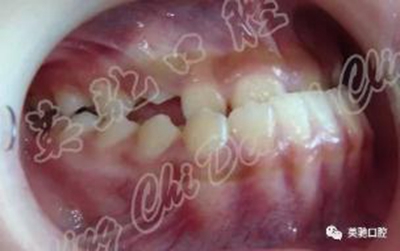

女性,就診時14歲。主訴:雙側耳屏前彈響3年。診斷:AngleⅢ類前牙反牙合。上頜發(fā)育不足,下頜前突,下前牙代償性舌傾明顯,右側上頜尖牙尚未完全萌出。雙側顳頜關節(jié)彈響,耳鳴。

治療:戴用小型下頜雙側調(diào)位牙合板后退下頜,同時粘固直絲托槽排齊整平上下牙列(除右上尖牙外)。在戴用后退位牙合板一月后,雙側關節(jié)彈響及耳鳴消失,繼續(xù)戴用共7個月。